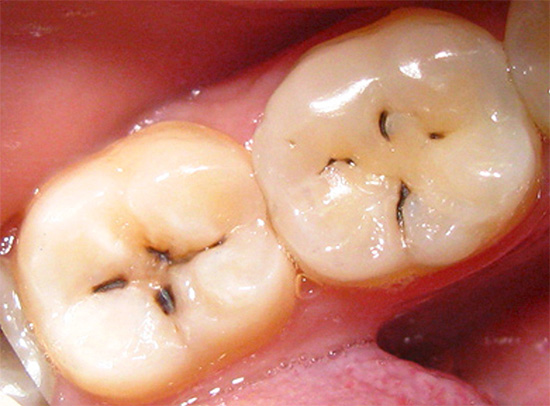

L'ispezione visiva dei denti è il modo principale per identificare una situazione cariogena nella cavità orale. La carie è caratterizzata dal fatto che in quasi tutte le fasi del suo corso, cambia il colore dello smalto dei denti. Anche nella fase spot, quando la dentina non è ancora interessata, lo smalto cessa di essere liscio e lucido e il dentista attento nota facilmente un tale cambiamento.

In fasi successive, determinare la carie con un semplice esame è ancora più semplice: porta alla comparsa di punti neri e marrone scuro sui denti o quando la dentina è danneggiata, sotto lo smalto sono visibili cavità scure.

Non sorprende, nella maggior parte dei casi, la diagnosi visiva della carie dentale può rivelare la maggior parte delle aree interessate. Con lei, il dentista esamina attentamente i denti da diversi lati con uno specchio. Inoltre, il medico può eseguire una sonda sonda: in luoghi dello sviluppo precoce del processo cariato, si avverte chiaramente la rugosità della superficie dello smalto.